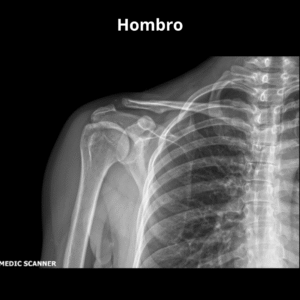

- Hombro AP O Derecho O Izquierdo